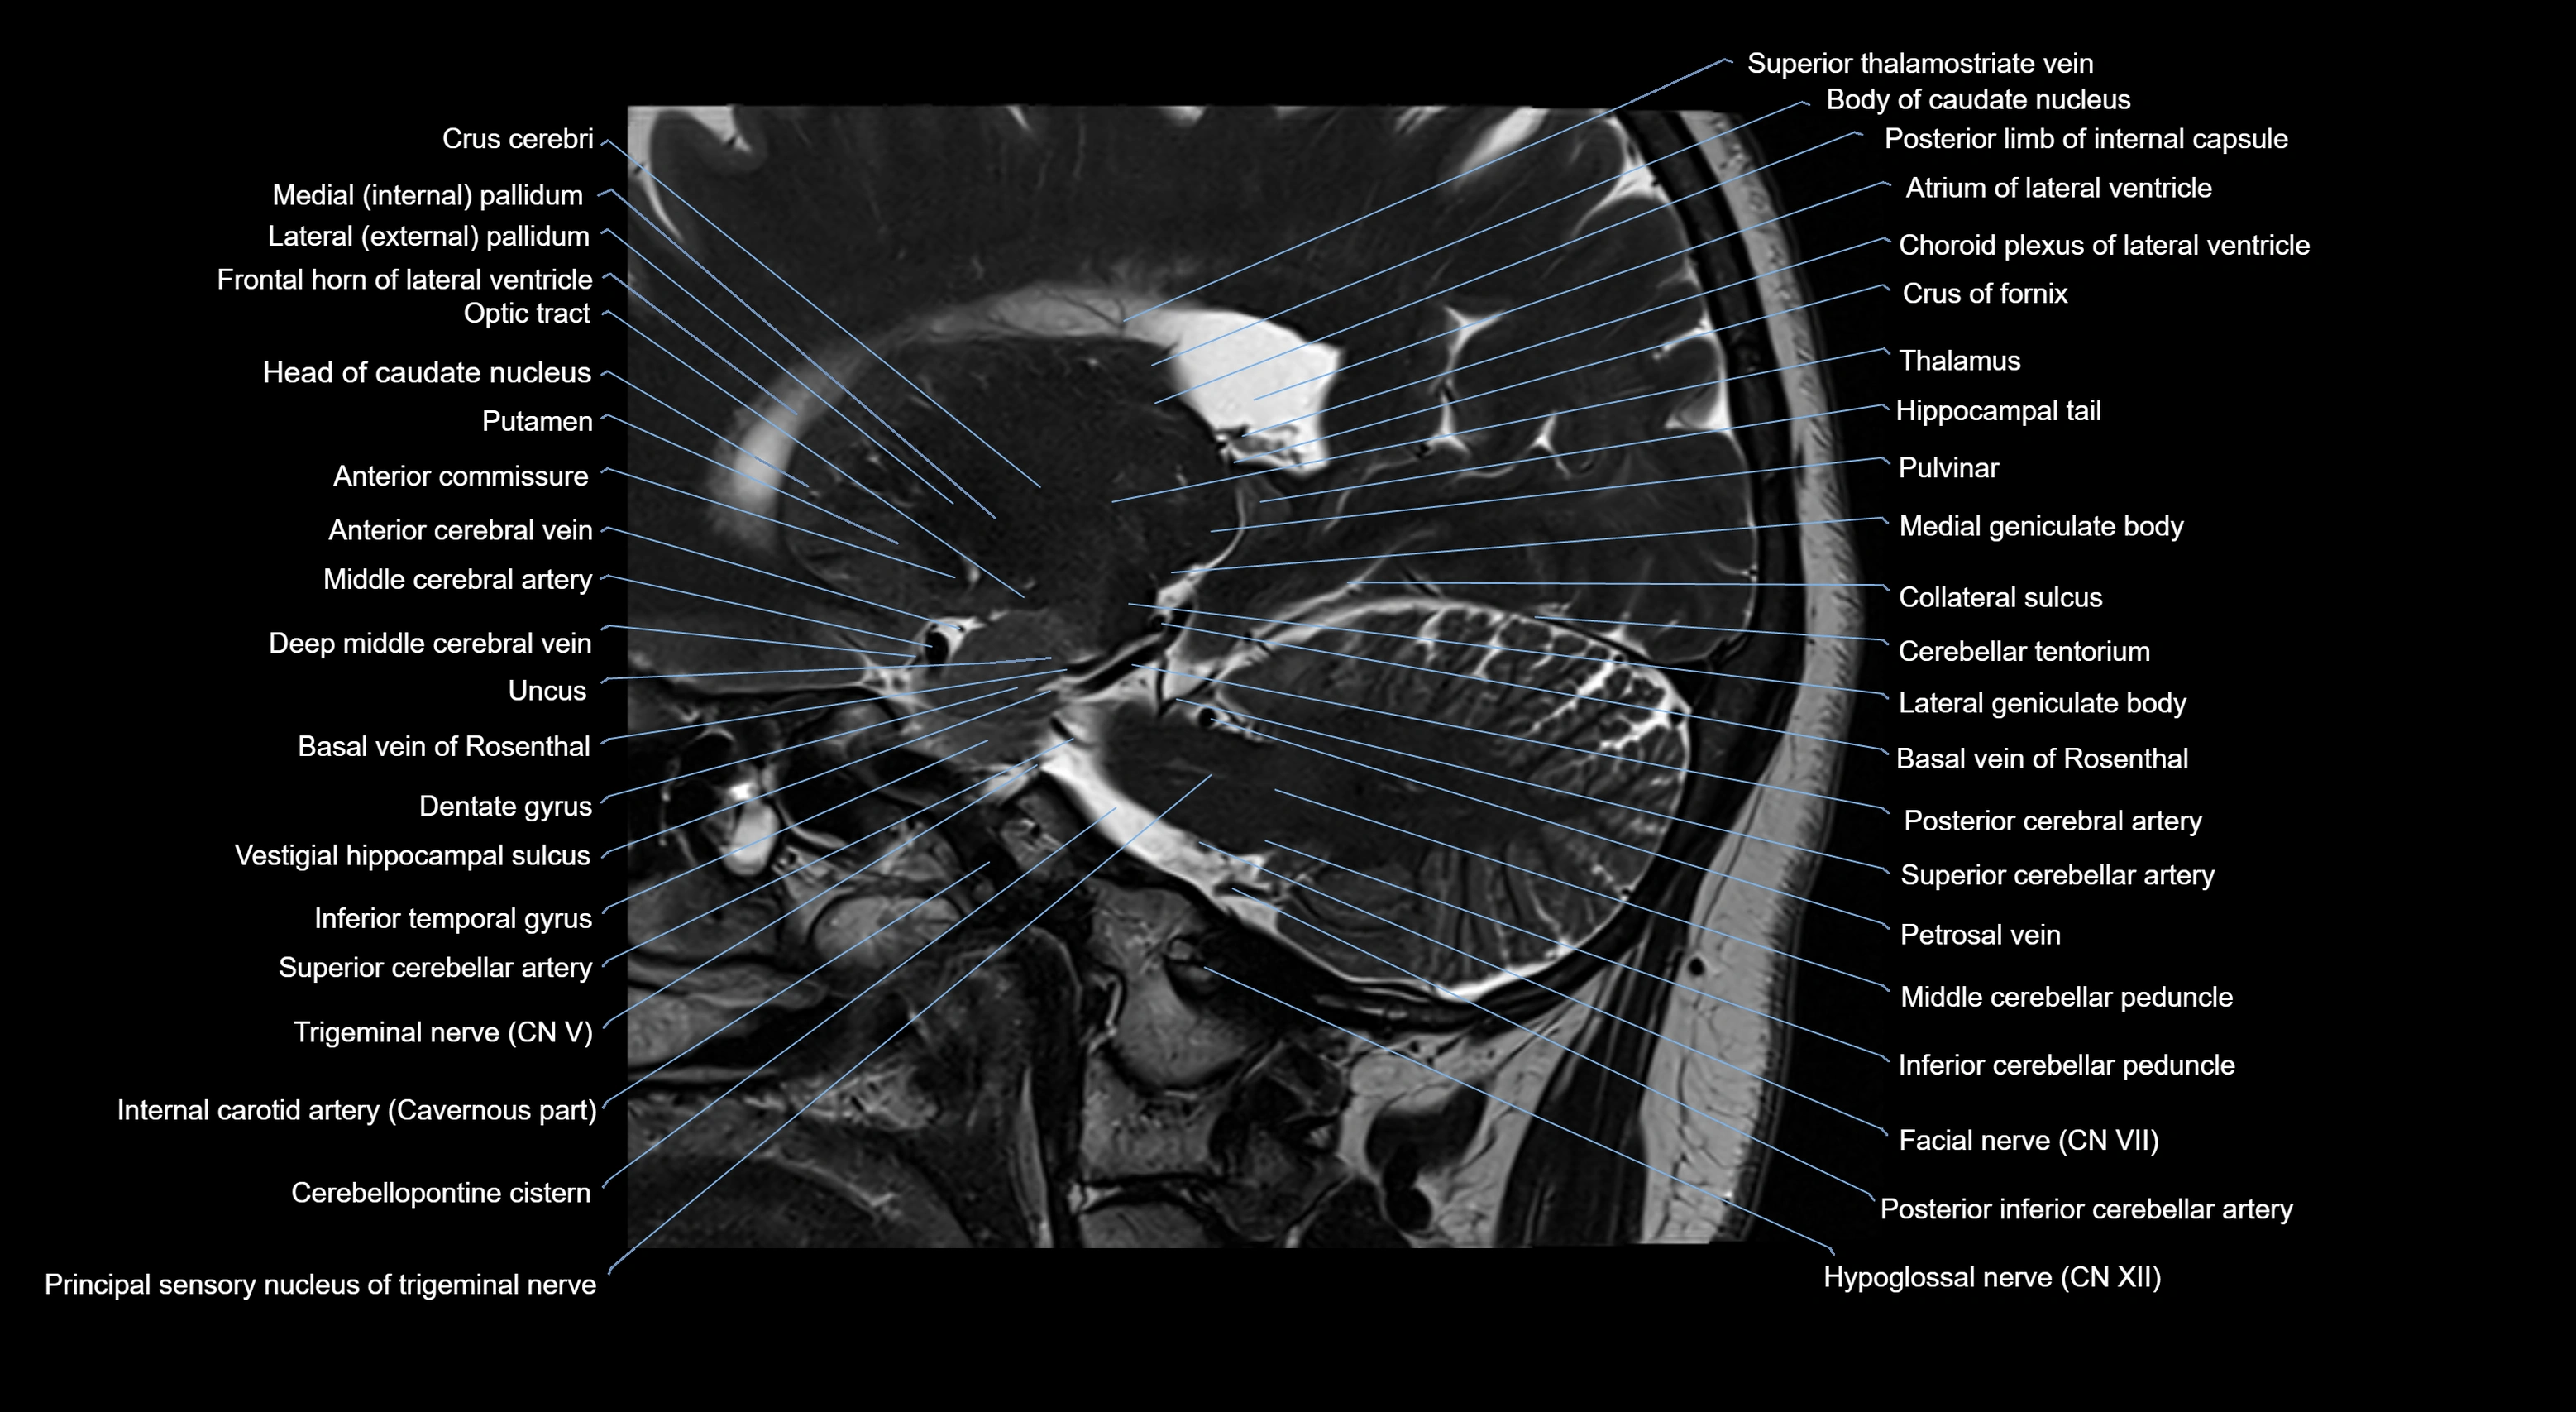

MRI images